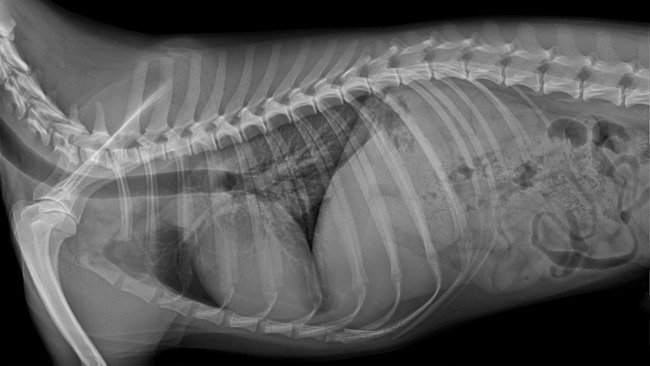

Stefan to kundelek z domieszką beagla. Został adoptowany przez nas rok temu z Krakowskiego schroniska jako szczeniak. To była nasza najlepsza decyzja. Wnosi do naszej rodziny wiele szczęścia. Jest jak nasze 3 dziecko. Kocha ludzi, kocha życie. Jednak mimo młodego wieku już dużo przeszedł. Już w 6 miesiącu swojego życia zaczęła się jego choroba. Stefek z energicznego psiaka w sekundzie stał się apatyczny, miał gorączkę, nie jadł, nie pił, nie wstawał, trząsł się z bólu. Pierwsza diagnoza była powiązana z zapaleniem pęcherza, jednak nie trafna. Niedługo później ataki powróciły. Po wykonaniu mnóstwa badań stwierdzono u niego najprawdopodobniej SRMA steroidozależne zapalenie opon mózgowo-rdzeniowych. Jednak żeby mieć pewność potrzeba jest dalsza diagnostyka w tym tomografia komputerowa i pobranie płynu mózgowo-rdzeniowego. Są to bardzo kosztowne badania, bez których się nie obejdzie.